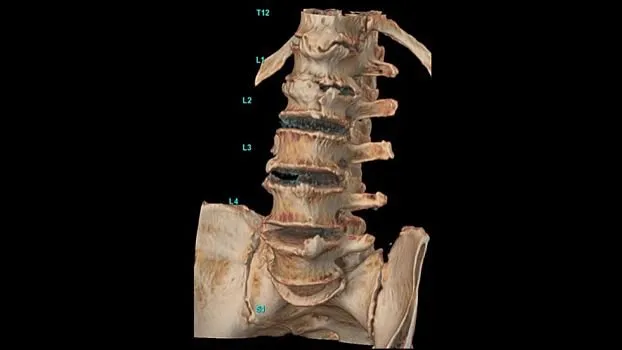

Клинические изображения

Revolution Ascend позволяет выполнять КТ-исследования быстрее, проще и удобнее, при этом получая изображения высокого качества. Интеллектуальные рабочие процессы, интуитивно-понятный пользовательский интерфейс и передовые технологии упрощают, оптимизируют и автоматизируют весь процесс компьютерной томографии.

Технология TrueFidelity

Revolution Ascend поддерживает технологию TrueFidelity**, которая реконструирует изображения с помощью алгоритмов глубокого обучения. Она обеспечивает глубокую детализацию, естественную текстуру, высокую контрастность и четкость изображений. TrueFidelity генерирует изображения с помощью алгоритмов искусственного интеллекта. Это позволяет, с одной стороны, использовать низкую лучевую нагрузку, как при итеративной реконструкции, а с другой стороны, получать изображения, не уступающие по качеству методу фильтрованных обратных проекций.